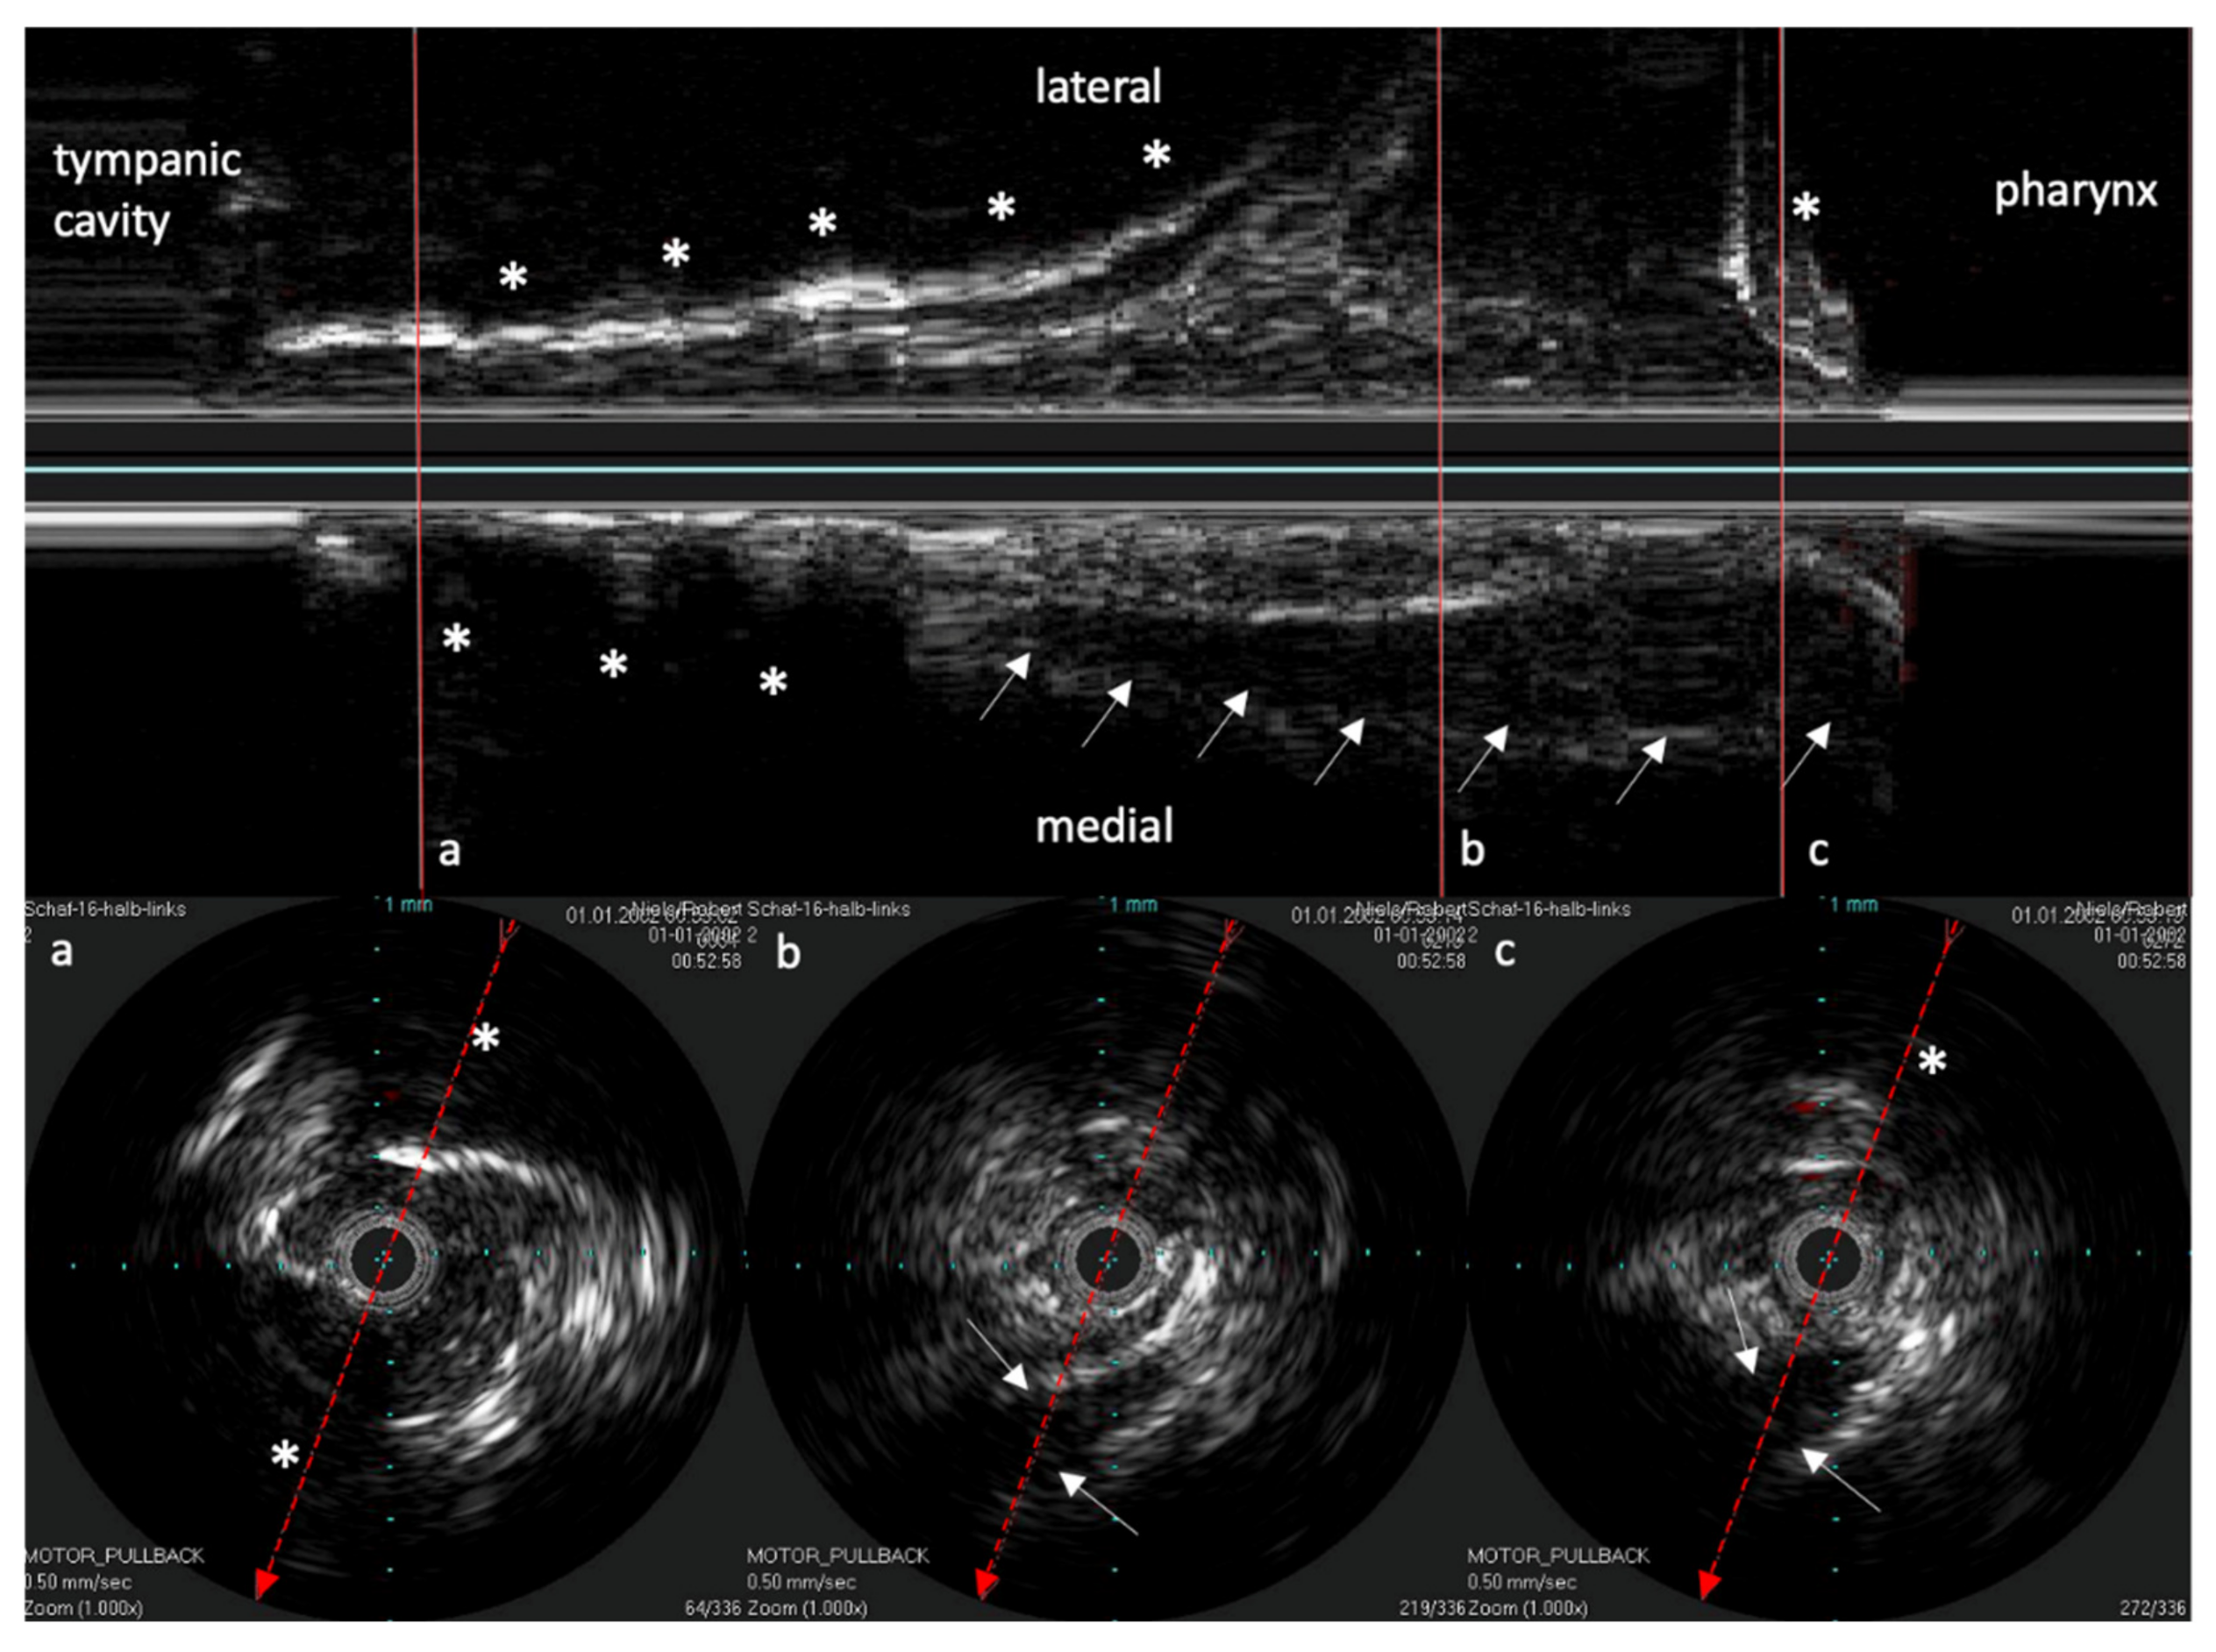

The reconstructed longitudinal view of the IVUS scans, as shown in Figure 4 with the corresponding circular views, was then compared with the 3D model and the corresponding histological sectional images of Schuon et al., 2021 [24] (Figure 5). Based on this, the surrounding structures could be identified in the IVUS image.

Figure 4. Longitudinal image of the ET with the corresponding cross sections. (a) near the ET isthmus. (b) in the middle section of the ET. (c) near the pharyngeal ostium. Bone is marked with *. The bony structures represent consistent topographic landmarks. The cartilage of the ET shows low echogenicity (white arrows). Note that the dashed red line in the cross-sectional image represents the axis of the longitudinal image. The tip of the arrow points toward the lower part of the longitudinal image.